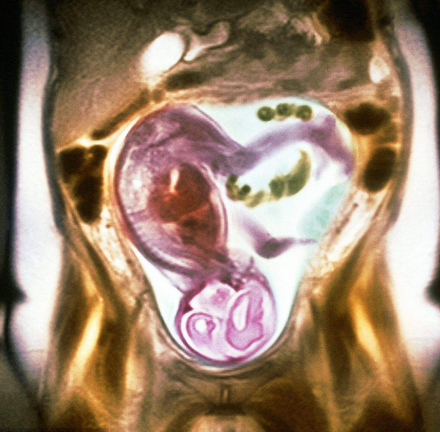

胎儿磁共振(MRI)的优势

不存在电离辐射;软组织分辨率高;视野大,可以任意切面扫描,显示胎儿全貌;受母亲情况影响小;不受胎儿骨骼及羊水量影响;对胎儿中枢神经系统疾病、羊水过少相关疾病和胸部疾病诊断方面有很高的准确性,在其他部位图像有良好的直观性和分辩率,并能量化评价肺发育不良。对于双胎及孕周较大时影像显示明显优于超声检查,特别是孕晚期胎头入盆或胎儿颅骨骨化时;胎儿 MRI 可进行任意切面扫描,精确地进行各种测量,对于胎儿疾病的定性较好,还可进行功能成像如磁共振波谱成像(MRS);MR 图像受检查操作者技术水平影响较小,便于保存和会诊。